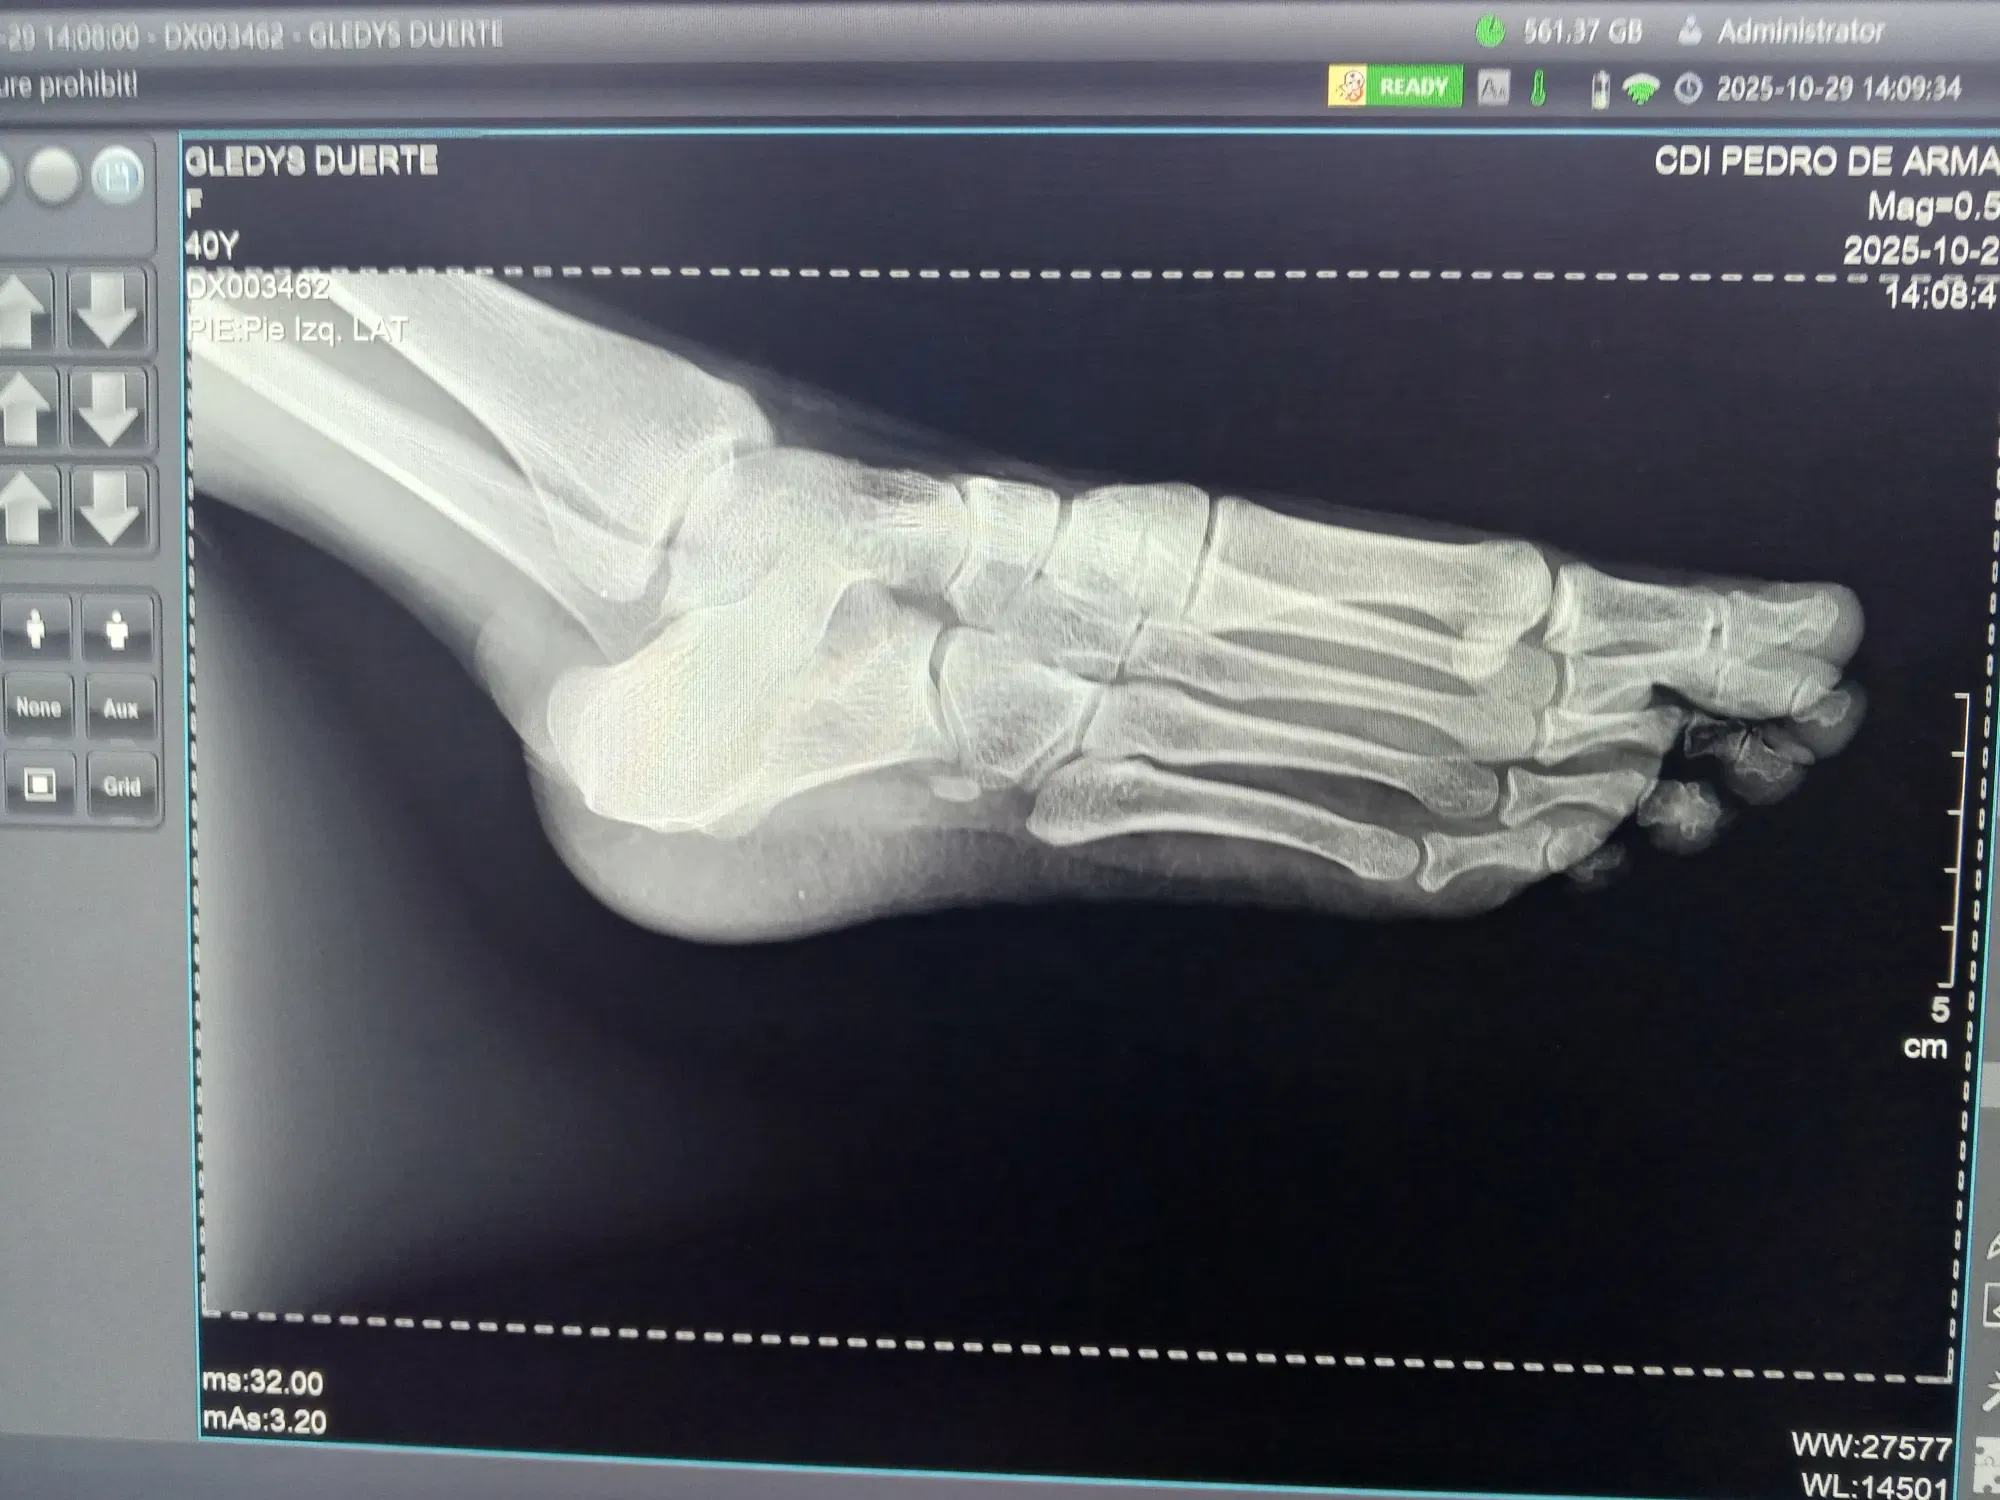

Estuve desde las diez y la consulta comenzaba a la 1. Mi hija llegó minutos antes. Yo aproveché y pase a consulta y pasé por un dolor en el talón que no se me quita. Me dieron orden para rx de pie y alcance número también.

I was there from ten o'clock, and the appointment started at 1. My daughter arrived a few minutes early. I took advantage of the situation and went to the consultation and mentioned a pain in my heel that won't go away. They gave me an order for an X-ray of my foot and a number as well.